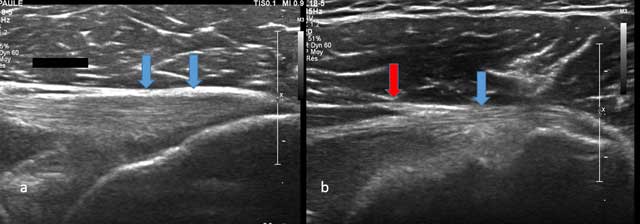

Figure 1

Axial view of Teres Minor with tendon (blue arrow) and musculotendinous junction (red arrow).